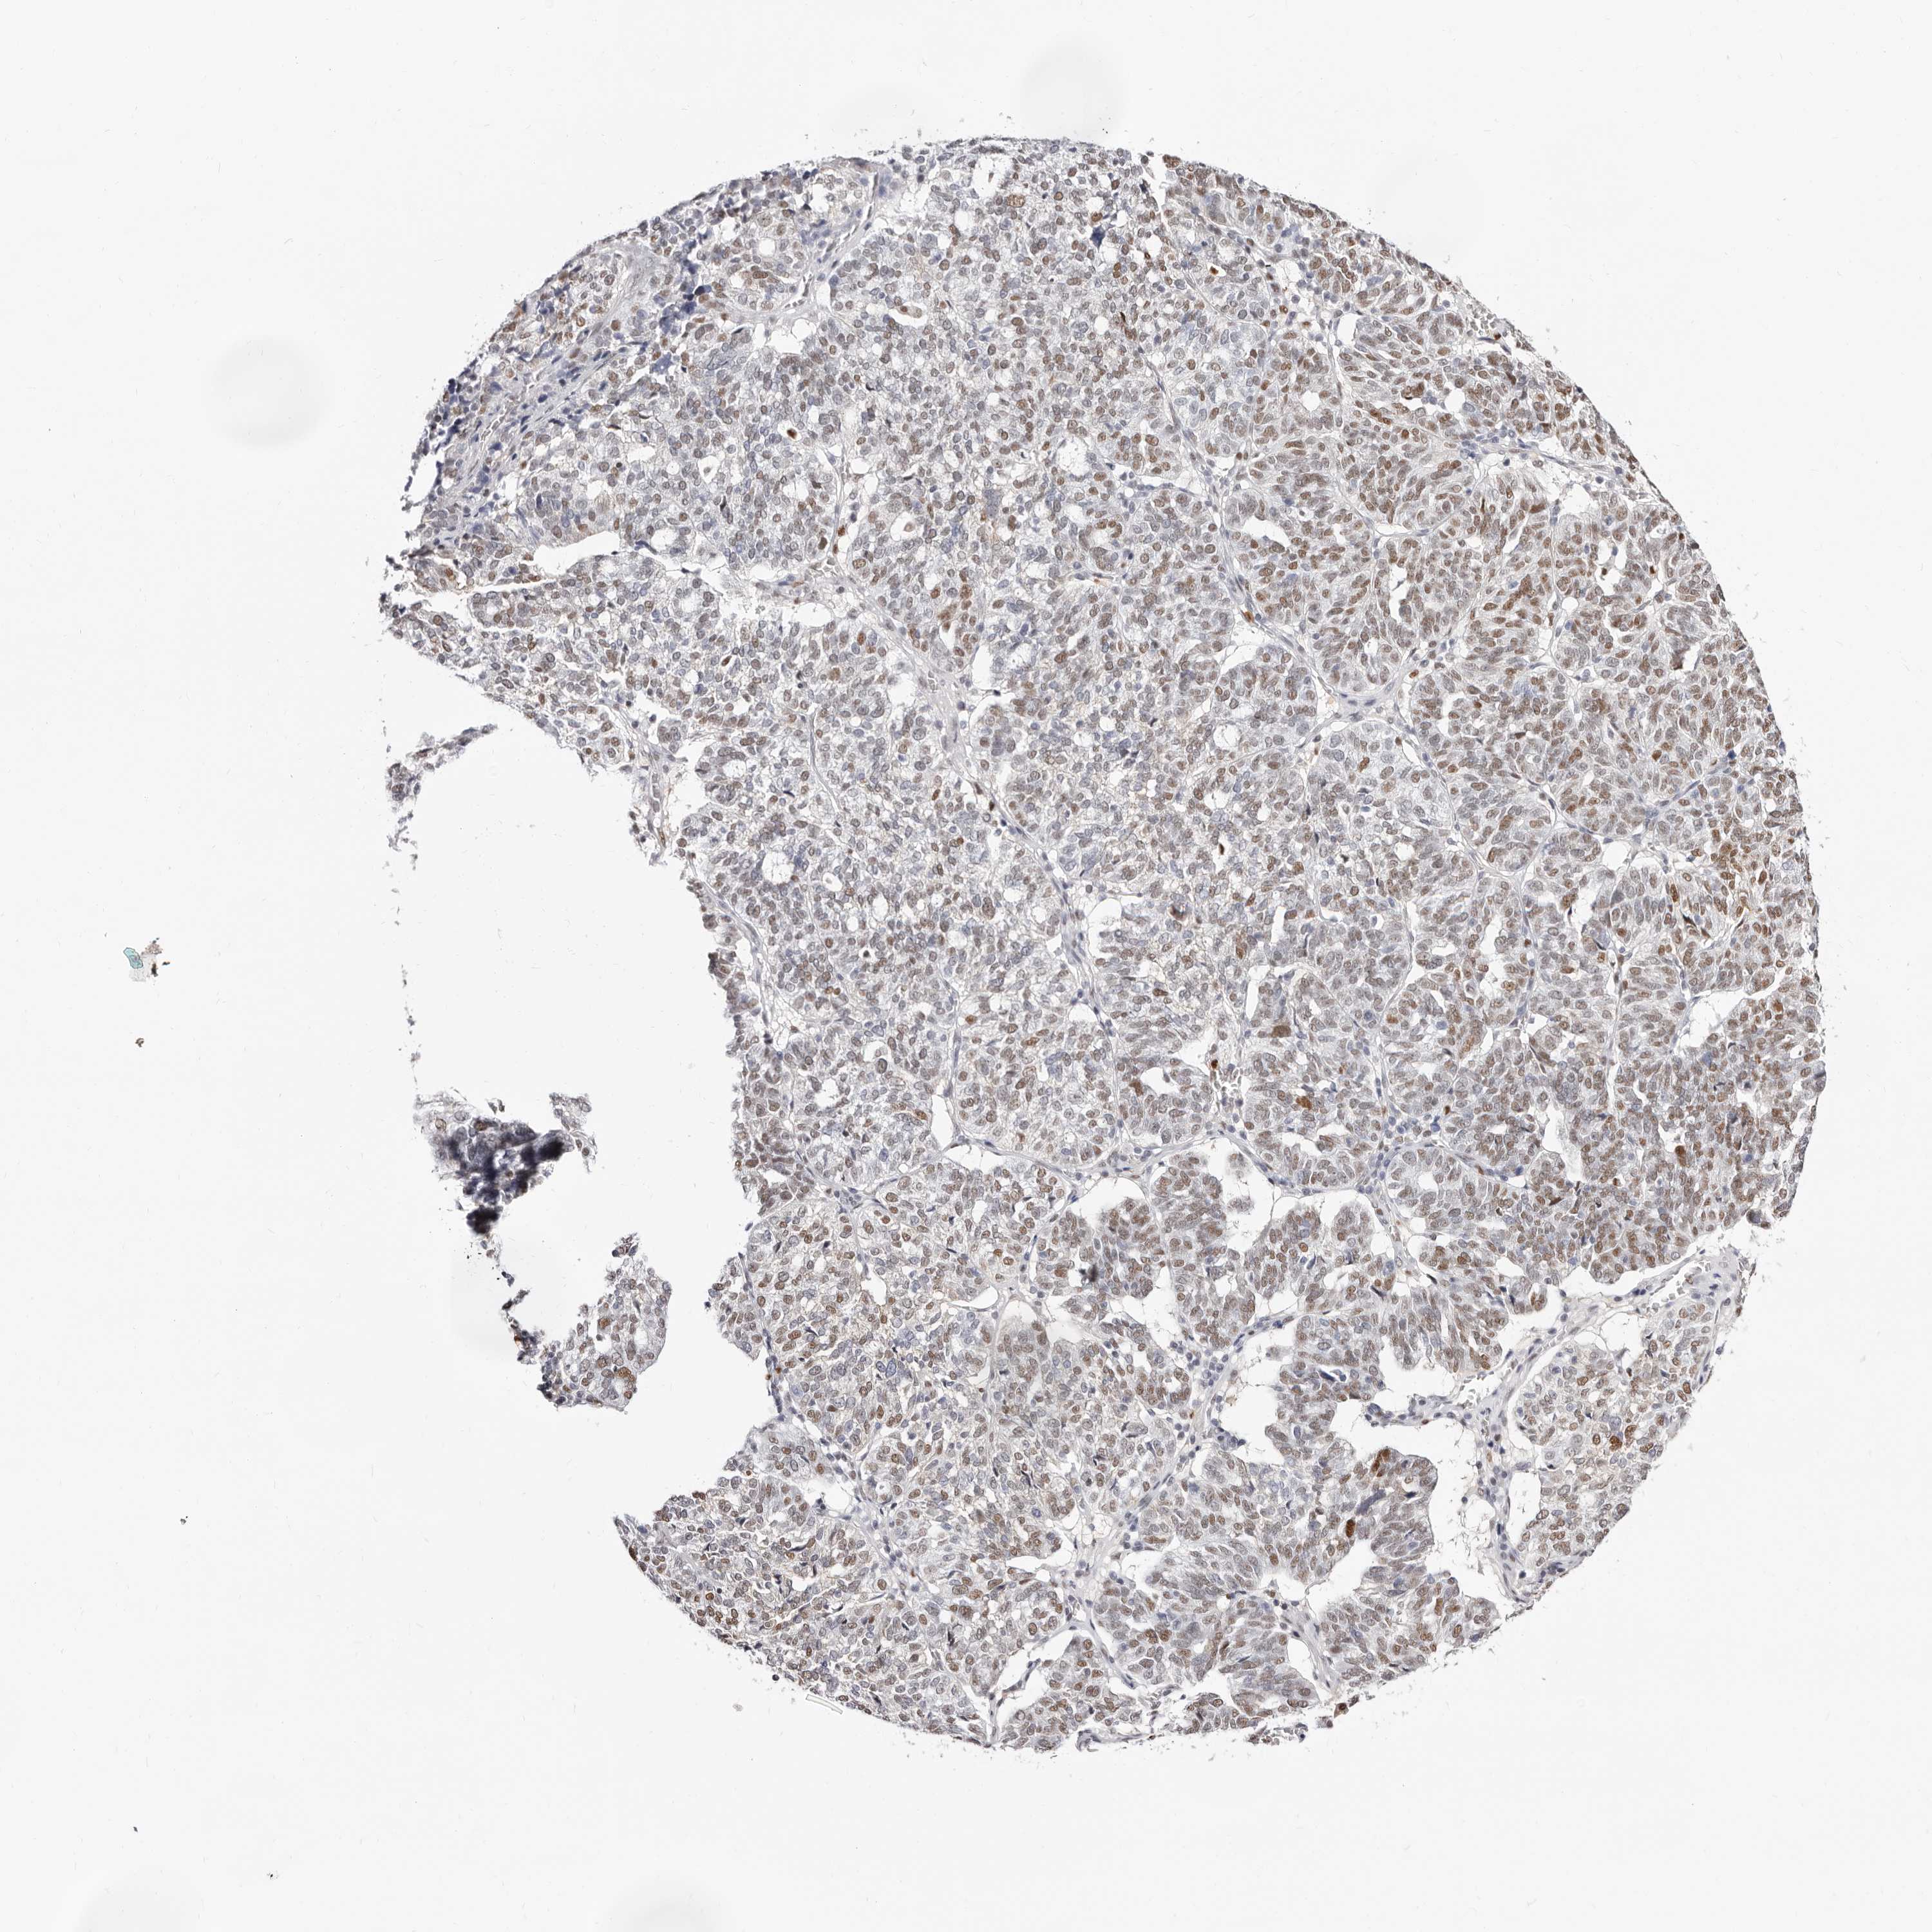

OVARIAN CANCER - Protein expressioni

A mouse-over function shows sample information and annotation data. Click on an image to view it in a full screen mode. Samples can be filtered based on level of antibody staining by selecting one or several of the following categories: high, medium, low and not detected. The assay and annotation is described here.

Note that samples used for immunohistochemistry by the Human Protein Atlas do not correspond to samples in the TCGA dataset.

Antibody stainingi

Antibody staining in the annotated cell types in the current human tissue is reported as not detected, low, medium, or high, based on conventional immunohistochemistry profiling in selected tissues. This score is based on the combination of the staining intensity and fraction of stained cells.

Each image is clickable and will lead to virtual microscopy that enables deeper exploration of all samples and also displays staining intensity scores, fraction scores and subcellular localization as well as patient and tissue information for each sample.

Antibody HPA029480

Antibody HPA029481

Cystadenocarcinoma, serous, NOS